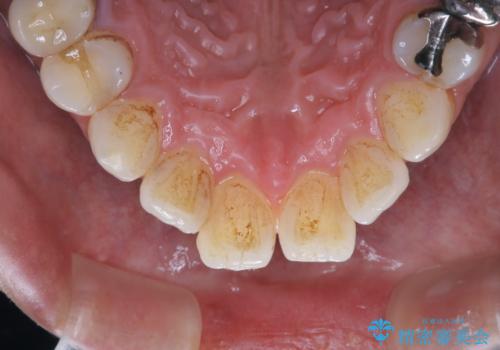

半年に一度クリーニングしているとのことでした。タバコとコーヒーの着色でした。

着色に厚みがあるため、エアーフローも使用して除去しました。

エアフローとは、歯面清掃を行う器具の一種で、非常に細かなパウダーを強力なジェット水流で歯に吹き付け汚れを落とす器具です。水圧とパウダーの力で隅々まで着色やバイオフィルムを効果的に、そして短時間で落とすことができます。